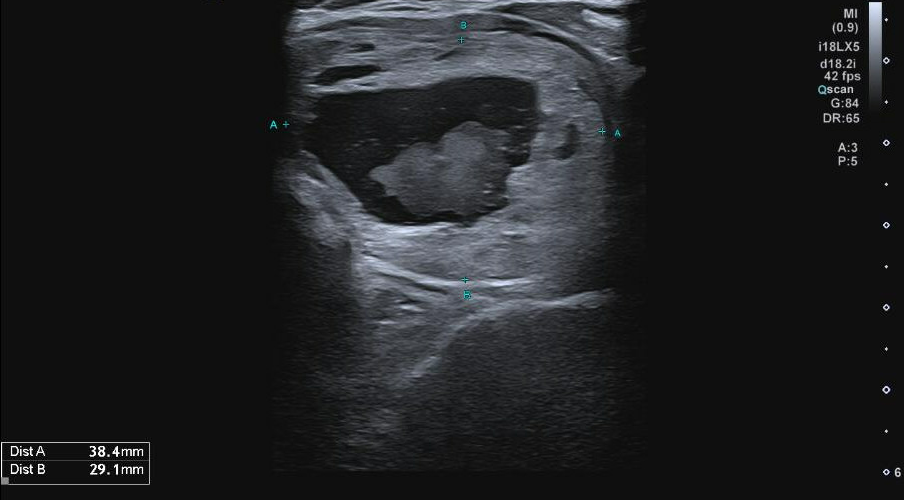

Ecografía tiroidea en consulta:

Ecografía reglada + PAAF (Servicio de Radiología):

Bocio multinodular con nódulo TIRADS 2 de 4,4 cm en LTI (Bethesda II).

En ecografía de control tras vaciamiento de componente quístico: nódulo mixto de predominio sólido, con porción quística central previamente vaciada, que vuelve a rellenarse de coloide/material hemático, conservando su tamaño.